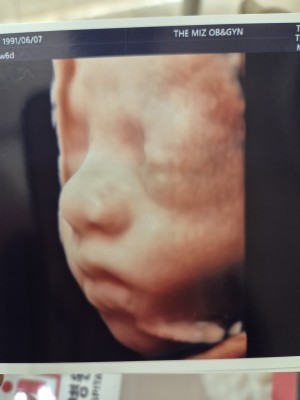

입초 두번째 만에 얼굴보여준 너!

닉네임_윤*영_5

2025-08-22

2

0